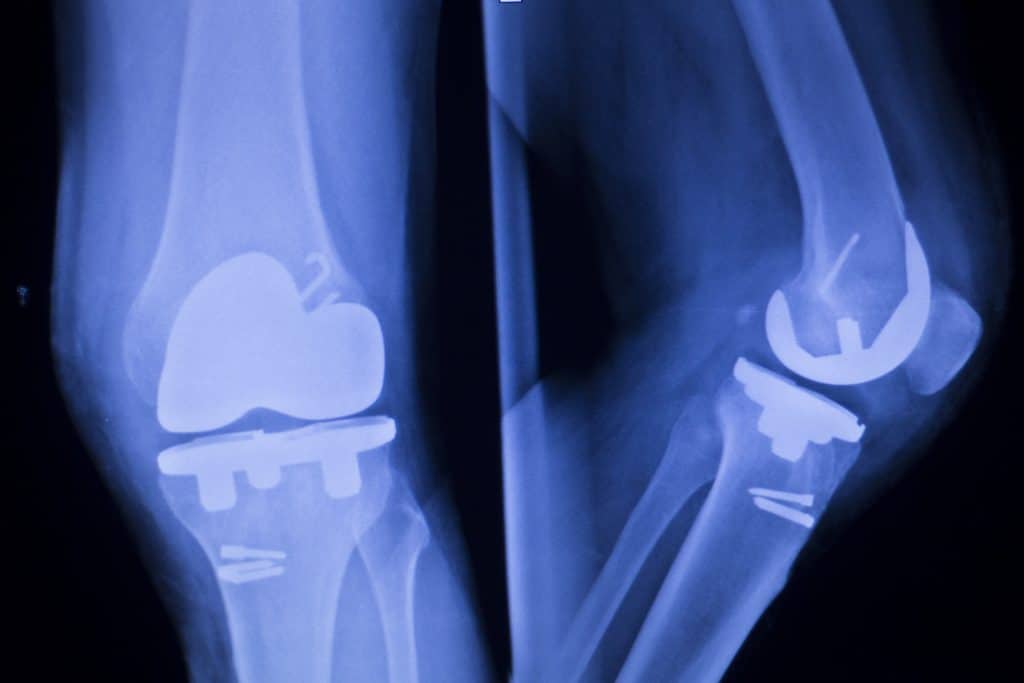

Uma descoberta particularmente útil em um país onde são feitas mais de 85.000 substituições de quadril e joelho anualmente – seja pelo envelhecimento da população, lesões esportivas ou efeitos da obesidade.

Infecções associadas a implantes continuam sendo um desafio crítico em cirurgia e ortopedia, já que antibióticos sistêmicos estão cada vez mais ineficazes devido à resistência, e cimentos com antibióticos costumam ter vida curta e espectro de ação estreito, afirmam os pesquisadores.